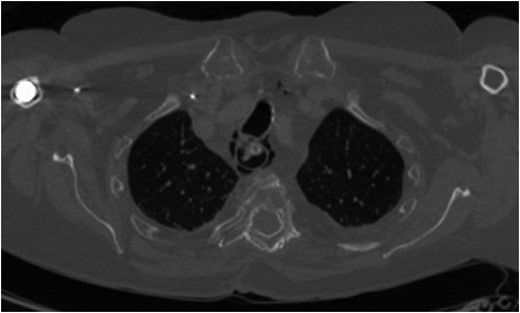

A 69-year-old woman who was previously well, with no history of steroid or non-steroidal anti-inflammatory use, was referred to our unit with an iatrogenic oesophageal perforation. She had undergone a laparoscopic cholecystectomy 5 weeks earlier, complicated by a secondary intra-abdominal bleed requiring laparotomy and splenectomy. The post-operative period was further complicated by small bowel obstruction secondary to internal herniation. This required an emergency laparotomy during which a posterior gastric perforation was identified (Fig. 1). Prior to transfer to our unit, the patient had undergone an upper GI endoscopy and attempted endoscopic placement of a VAC therapy device in order to treat this gastric perforation. Whilst attempting to progress the sponge component of the VAC device, the patient suffered an iatrogenic oesophageal injury. Computed tomography (CT) imaging demonstrated mediastinal emphysema, confirming a full thickness tear of the cervical oesophagus (Fig. 2).

Axial CT scan (bone window) demonstrating mediastinal emphysema as a result of iatrogenic cervical oesophageal perforation.